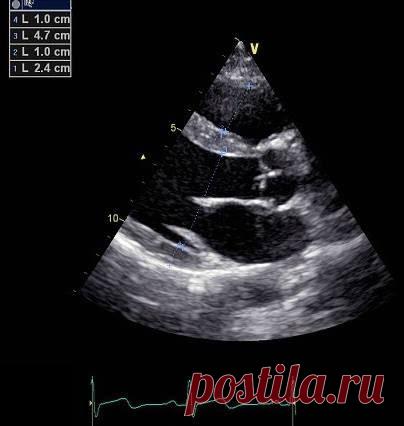

Эхокардиография для чайников, часть 1. Линейные измерения